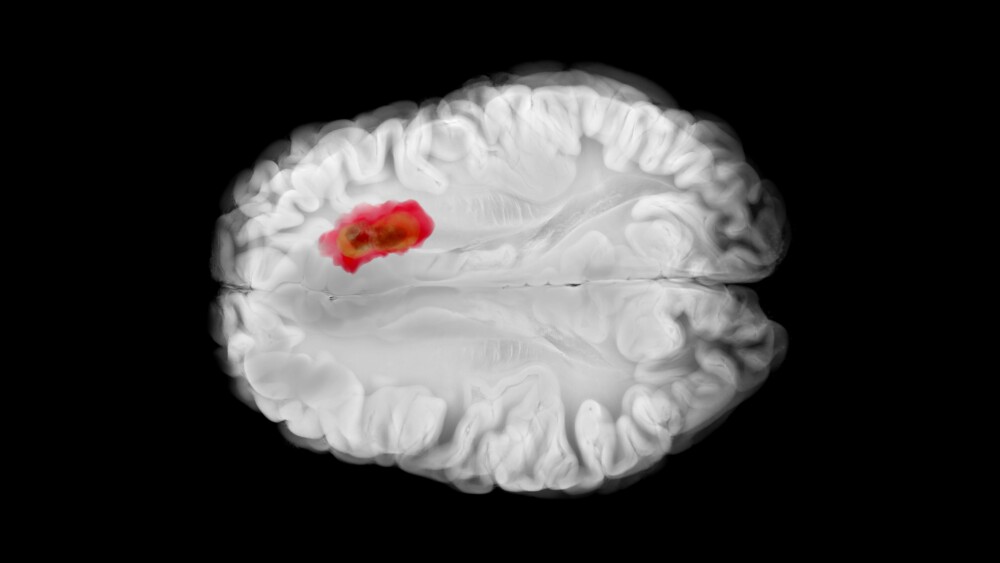

City of Hope researchers led a team that performed bulk RNA sequencing, tumor/normal DNA sequencing and spatial transcriptomics in a small sample of gliomas — tumors that develop in the brain or spinal cord. Through varied experiments and validation cohorts, they were able to identify common and distinct characteristics of the tumor microenvironment, developing an integrated analysis framework that can be leveraged by others.

The researchers demonstrated that ecDNA drives rapid cancer cell (oncogene) proliferation outside of chromosomes, the thread-like structures inside the cell nucleus that houses DNA and RNA. EcDNA contributes to the development of gliomas, genetic instability and distinct tumor cell populations within a single tumor, making cancer more difficult to eliminate.